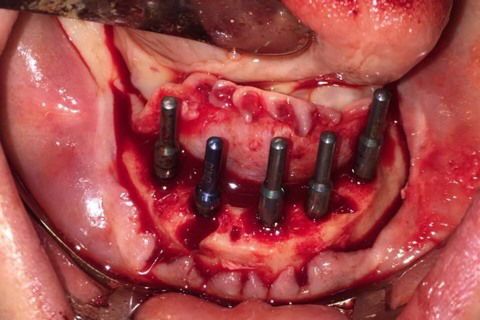

Paciente com síndrome de kelly,foi feito exodontia do 33 ao 43,regularização da tábua óssea e colocação de 5 implantes Implacil UN2 cônicos HI de 4x12,em seguida foi feito procedimento protetitico.

Fotos do caso